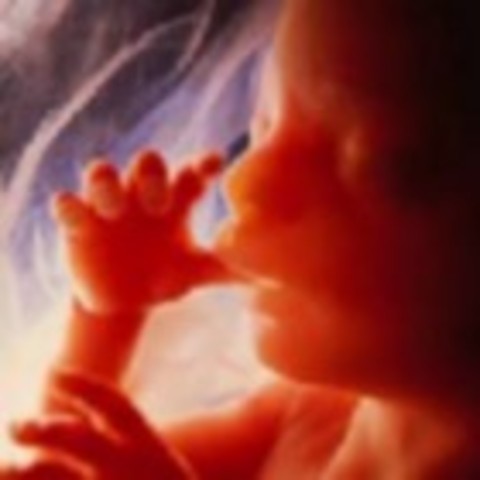

• week 12

week 12

The most dramatic development this week: reflexes. Your baby's fingers will soon begin to open and close, his toes will curl, his eye muscles will clench, and his mouth will make sucking movements. In fact, if you prod your abdomen, your baby will squirm in response, although you won't be able to feel it. His intestines, which have grown so fast that they protrude into the umbilical cord, will start to move into his abdominal cavity about now, and his kidneys will begin excreting urine into his